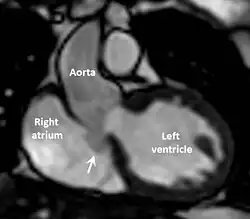

| Diagnostic method | Echocardiogram, cardiac CT scan, cardiac MRI scan |

The first step in diagnosis is typically transthoracic echocardiography. However, if surgery is planned or if the standard echocardiogram lacks sufficient detail, then one or more additional studies are recommended. These studies include transesophageal echocardiography, 3D echocardiography, CT Angiography and aortic angiography.[4] Cardiac MRI may be another option.[2]